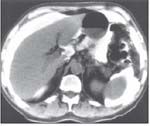

FIGURE 3

IP contrast computerized tomography study showing optimal distribution of drug to peritoneal surfaces.

• Drug delivery is generally more satisfactory in patients selected for IP therapy based on low-volume disease[19] (Figure 3);